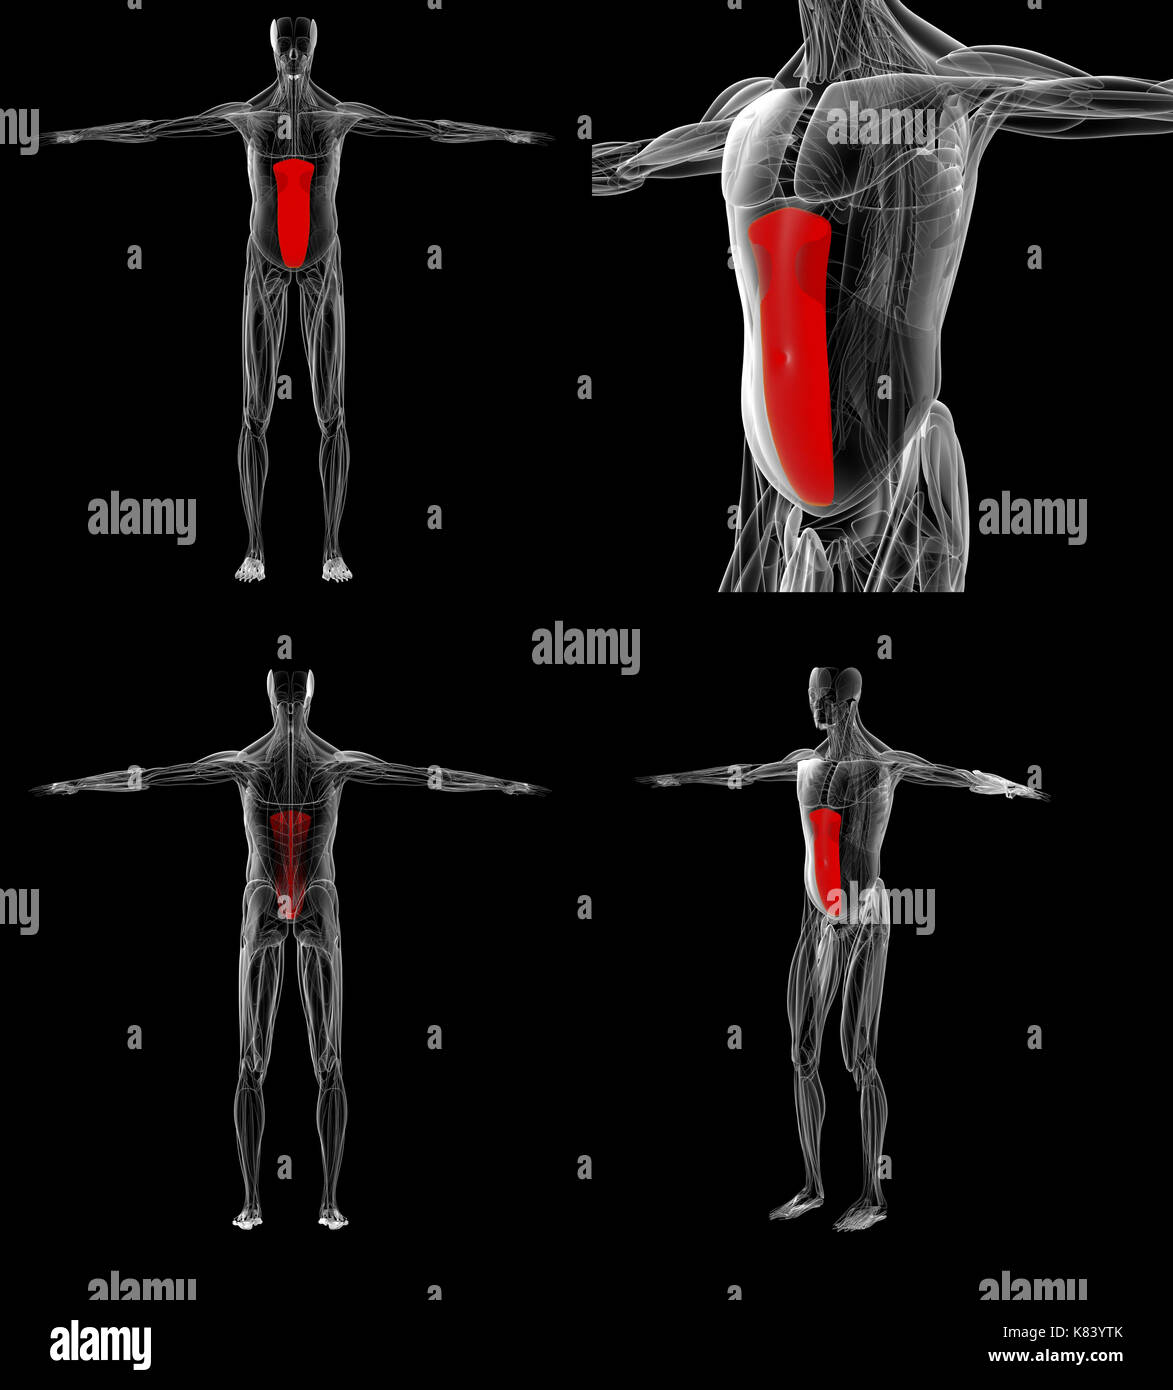

Human Muscles Abdomen Muscles Anatomy Medical Stock Illustration

3d Rendered Illustration Of The Abdominal Muscles Stock Photo - Alamy

www.alamy.comabdominal

www.alamy.comabdominal

3d Abdomen Abdominal Anatomical Hi-res Stock Photography And Images - Alamy

www.alamy.comrectus abdomen rendering accurate medically abdominis

www.alamy.comrectus abdomen rendering accurate medically abdominis

3d Abdomen Abdominal Anatomical Stock Photos & 3d Abdomen Abdominal

www.alamy.comabdominal anatomy abdomen 3d illustration accurate medically human stock alamy anatomical

www.alamy.comabdominal anatomy abdomen 3d illustration accurate medically human stock alamy anatomical

Male muscle anatomy of the abdominal wall poster print (26 x 30. Abdomen (human anatomy). 3d rendered illustration of the abdominal muscles stock photo